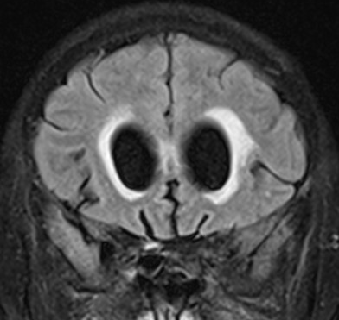

2013-5-16 MRI